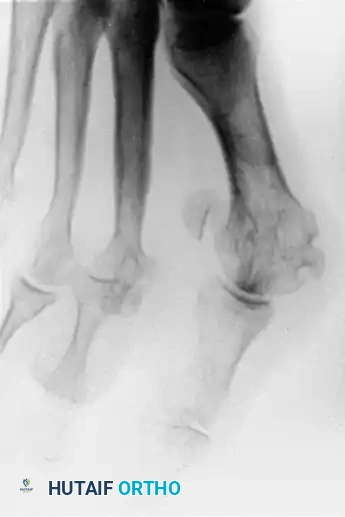

Patients typically present with intractable metatarsalgia, dorsal PIP joint ulcerations, and a palpable, dorsally displaced proximal phalanx base. Weight-bearing anteroposterior, lateral, and oblique radiographs are mandatory to assess the degree of dorsal subluxation or frank dislocation, the relative lengths of the metatarsals, and the presence of degenerative joint disease.

Clinical appearance of a severe hammer toe deformity with chronic dislocation of the metatarsophalangeal joint.

Preoperative radiographic evaluation demonstrating dorsal dislocation of the MTP joint.